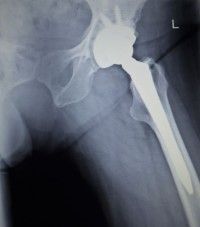

hip-replacement-lawsuitA California woman alleges Biomet failed to adequately warn the Biomet Magnum metal-on-metal hip system poses an unreasonably high risk of premature failure and other dangerous hip implant complications.

Plaintiff Maria D. filed this metal on metal hip implant lawsuit against Biomet, alleging she sustained severe hip replacement injuries as a result of Biomet’s defective manufacturing and marketing of the M2a Magnum hip implant.

Maria received the Biomet hip in February 2008 in a right total hip replacement surgery. According to the Biomet hip implant lawsuit, Maria had no initial complications following surgery but returned to her physician in October 2013, with severe pain and clicking in her right hip.  An x-ray showed complete failure of the acetabular cup, which was in a vertical position, the lawsuit says.